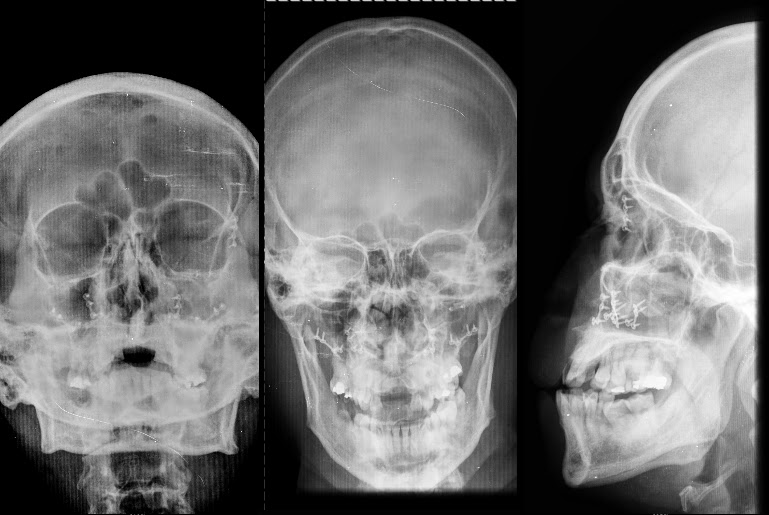

Radiografías en Cirugía Maxilofacial

Radiografía de Cadwell. Radiografía de Waters. 2.- Forma de realización del examen . Como toda radiografía, se toma en la sala de rayos. Se le pide al paciente que se siente en una silla, que mire hacia delante y fije su cabeza y se toma la proyección antero-posterior.. Estudio de la identificación de las distintas estructuras que podemos describir en una Rx de cráneo (water)